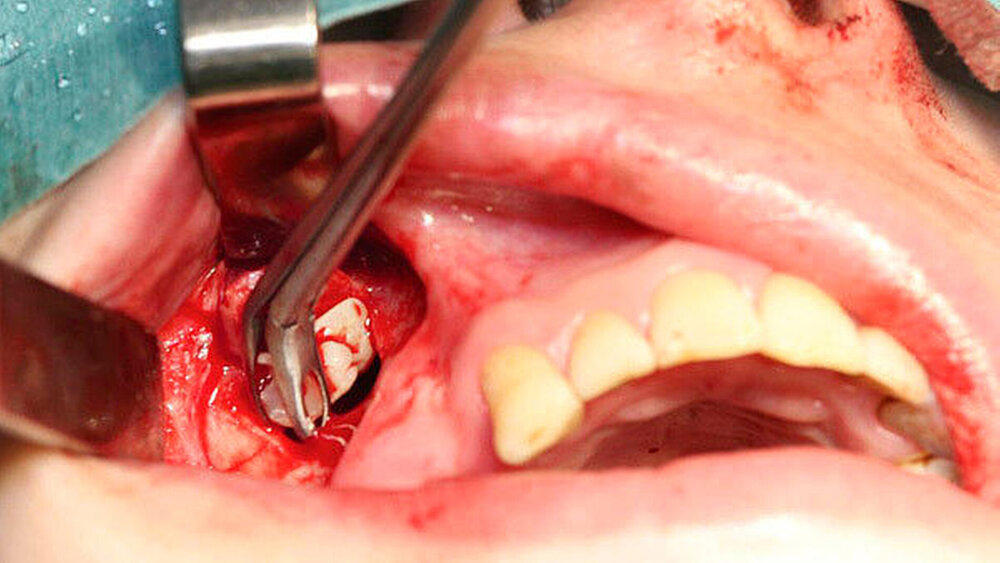

In Intubationsnarkose konnte der Fremdkörper aus dem rechten Sinus maxillaris über einen osteoplastischen offenen Zugang vestibulär regio 014 bis 015 geborgen werden (Abbildung 3). Die Mund-Antrum-Verbindung regio 026 wurde mittels eines Rehrmannlappens verschlossen. Gleichzeitig erfolgte die Entnahme von Proben aus bei den Kieferhöhlen. Die Abbildung 4 zeigt den kunststoffartigen Fremdkörper im Sinne von Füllungsmaterial. Die postoperative Röntgenkontrolle dokumentiert die Entfernung des Fremdkörpers (Abbildung 5) in toto.